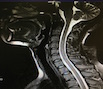

耳鼻咽喉-头颈外科

始创于1929年,前身成都存仁医院为东南亚最大的眼耳鼻喉专科医院,也是我国耳鼻咽喉科学的主要发源地之一。国内著名耳鼻咽喉科专家姜泗长、郑中立、卜国铉等曾在该科工作过。科室分别于1978年、1986年被批准为我国硕士学位、博士学位授予点, 1992年成为全国博士后流动站单位,并于2007年被正式指定为国家临床药物试验耳鼻咽喉专业基地,2010年获国家临床重点专科。 目前,科室有医师40人,护士34人,其中教授10人,副教授11人,博士导师4人,硕士导师10人。在职医生80%拥有博士学位,10多名医生先后赴英国、美国、加拿大、日本、比利时等国家攻读学位或研修学习。正式编制床位104张;门诊诊断室14间(含温江), 2018年门诊量达227869人次,出院7170人次,年手术7570台次;承担博士、硕士、本科生培养,住院医师规范化培训和国家自然科学基金、科技部支撑计划、国家教委博士点基金、卫生部、省科委多项科研任务。 临床工作:各亚专业设置齐全,发展迅速,各具特色,有技术专业化的学术带头人及合理的人才梯队。